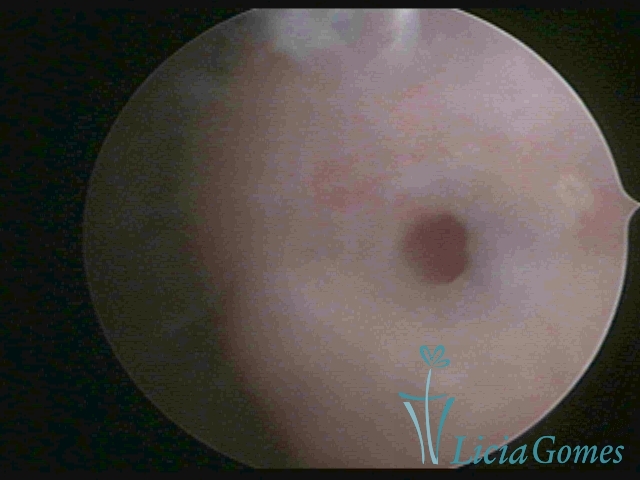

Third part or upper section

Presents the mucosa with a smooth, poorly vascularized surface, to the internal orifice